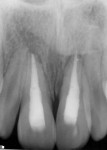

At presentation (Figure 1 through Figure 4), the patient was symptomatic with a dull ache. Teeth Nos. 8 and 9 were repositioned incorrectly, with tooth No. 9 being severely malpositioned. Upon examination, the patient was afebrile and alert and oriented times three. He stated that he did not lose consciousness at the time of the trauma. The patient’s vital signs were determined and considered normal. The patient had no history of significant medical disease, denied all medications, and had no known drug or food allergies. His review of systems was noncontributory for systemic disease. The patient’s head-and-neck examination exhibited no signs of facial fracture. A small laceration of his upper lip in association with tooth No. 9 was healing well. Teeth Nos. 8 and 9 were malpositioned, with tooth No. 9 being severely extruded. The remainder of his head-and-neck examination was unremarkable.

Teeth Nos. 8 and 9 were tender to percussion and palpation. Teeth Nos. 8 and 9 were nonresponsive to cold testing (Frigi-dent™, Ellman International, www.ellman.com). Teeth Nos. 8 and 10 were +1 mobile, while tooth No. 9 was +3 mobile. The gingival tissue around tooth No. 9 was erythematous. Periodontal probing depths were 3 mm to 4 mm generalized for all teeth except tooth No. 9, whose probing depths were 6 mm to 8 mm. Upon radiographic examination, teeth Nos. 8, 9, and 10 had widened periodontal ligament spaces. No other pathology was noted. The remainder of the examination was unremarkable.